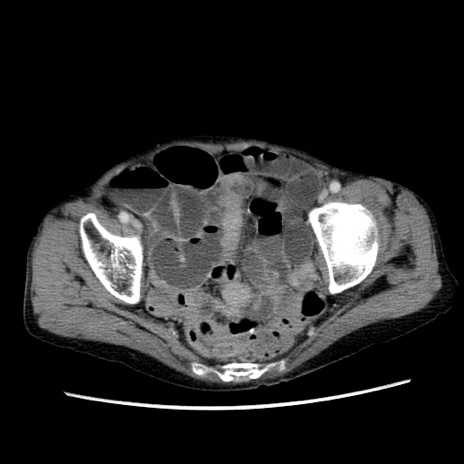

冠状断像

症例25(横断像)

【症例】80歳代女性

【主訴】胸のつかえ感

【現病歴】約9時間前に食後から胸のつかえた感じあり、嘔吐あり、来院。

【既往歴】胃癌(全摘)、胆摘、虫垂炎

【身体所見】心窩部に圧痛あり、反跳痛なし。

【データ】WBC 5700、CRP 0.05